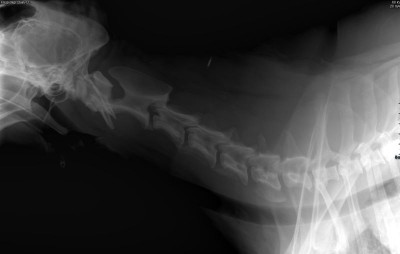

Niestety to nie koniec jego ortopedycznych problemów. W badaniu fizykalnym Pan doktor stwierdził zwiększoną bolesność odcinka lędźwiowo-szyjnego kręgosłupa. Na RTG kręgosłupa ma widoczne zmiany typowe dla zaawansowanej postaci zespołu końskiego ogona, zaawansowaną spondylazę a na domiar złego przewężenia w przestrzeniach międzykręgowych m.in. w odcinku szyjnym co ma wpływ na jego czucie (kwestie neurologiczne) i stanowi ryzyko paraliżu w przyszłości :(

Kręgosłup szyjny 1.jpg

Plik ściągnięto 10 raz(y) 24.56 KB